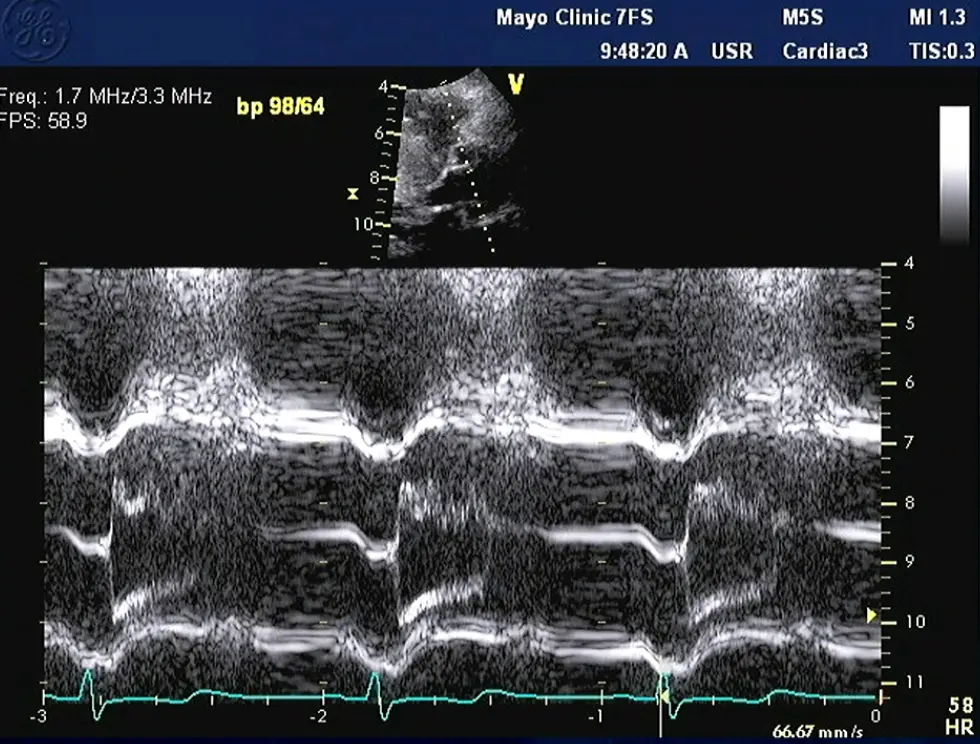

M-mode

- Temporal resolution of M-mode → the duration of SAM where it is in contact with the septum correlates w/ severity of LVOT obstruction

Notice the turbulence, which suggests LVOTO